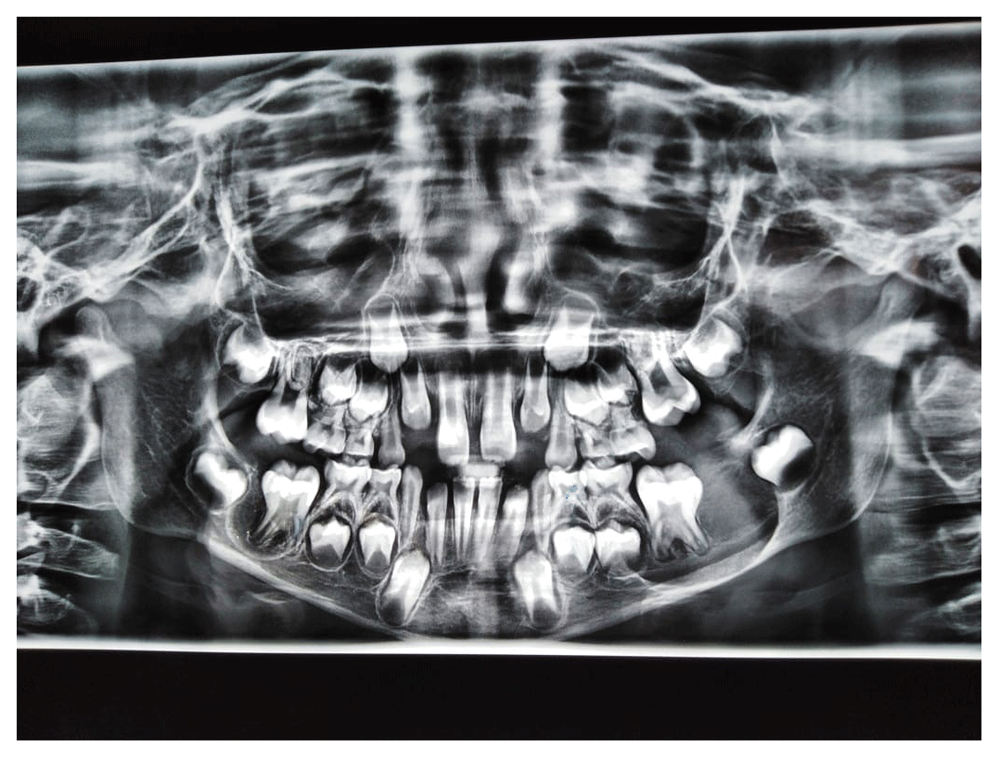

Diagnostic radiographs were taken. A panoramic radiograph illustrated bilateral, well-defined radiolucencies surrounded by sclerotic margins and including the unerupted incomplete permanent mandibular first molars (36 and 46, according to the FDI World Dental Federation Notation). The panoramic image showing right radiolucency measured around 1 cm in its greatest dimension, and involved the unerupted permanent mandibular first molar (46, according to the FDI World Dental Federation Notation), and not involving the inferior mandibular cortical bone and the adjacent areas. On the other hand, the left radiolucency measured around 3cm in its greatest dimension, and involved the unerupted permanent mandibular first molar (36, according to the FDI World Dental Federation Notation), the inferior mandibular cortical bone and the adjacent areas. Moreover, the left radiolucent cyst distally displaced the permanent mandibular second molar tooth bud (37, according to the FDI World Dental Federation Notation) (Figure 1). Provisional diagnosis of the bilateral lesions suggested bilateral BBC, dentigerous cyst, and paradental cyst.